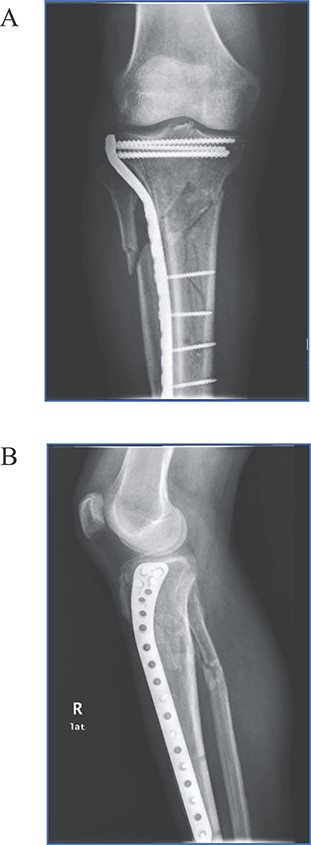

Three weeks after initial injury, minimally invasive osteosynthesis was performed using a 12-hole precontoured proximal lateral tibia plate (I.T.S., GmbH, Graz/Austria). Patient was draped and placed in supine position under spinal anesthesia: nonsterile pneumatic tourniquet was placed and inflated to 350 mmHg. The external fixator was removed, and an anterolateral incision was made on the right proximal tibia for fracture fixation. Insertion guide and plate were inserted between anterior tibialis muscle and periosteum. Insertion of screws was performed with the aid of C-arm fluoroscopy (for proper screw placement). After tourniquet was deflated, surgical incision was closed with sutures. During the procedure, no signs of brisk bleeding or damage to neurovascular structures were observed. Immediately after the procedure, the patient exhibited symmetrical palpable peripheral pulses of dorsalis pedis and posterior tibialis arteries. Postsurgical radiographic images revealed excellent fracture reduction and alignment (Fig. 2). Hospital stay was uneventful, and patient was discharged home the next day with pertinent postoperative management instructions.

(A) Anteroposterior and (B) lateral views of the right tibia following minimally invasive percutaneous osteosynthesis. Images reveal proper alignment and fracture reduction.